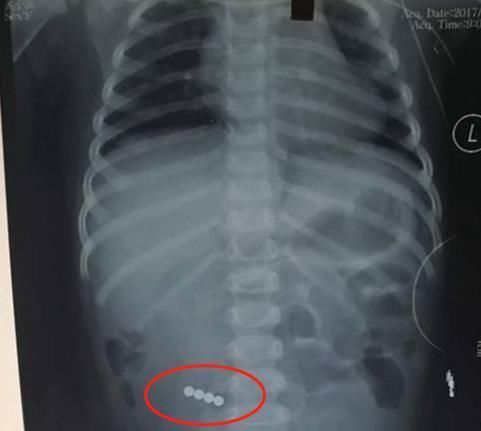

4、磁力钢珠

磁力钢柱之间互相有磁性,一颗碰到另一颗就会吸住,如果小朋友不小心将钢珠误食到肚子里面,它们很有可能会因为磁性,而导致相互连接在一起,最终因压力导致孩子身体器官受损,危害生命。而且小朋友长期接触这种彩色钢珠,很容易会引起重金属中毒,河南曾经有一名儿童因误食了磁力钢珠,导致发热腹痛,最终钢珠压迫肠壁,造成肠道多处穿孔,危险至极。